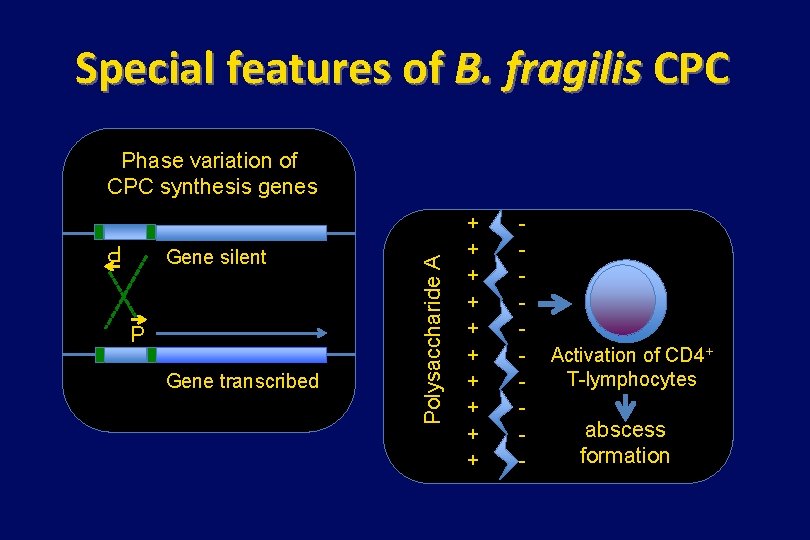

What’s special about B. fragilis ? 3. It has a complex capsular polysaccharide that is essential for abscess formation • Composed of at least 8 polysaccharides • Each is capable of transcriptional phase variation (synthesis genes preceded by an invertable region containing a promotor) • Polysaccharide A is essential for abscesses in animal models and is zwitterionic

Special features of B. fragilis CPC P Gene silent P Gene transcribed Polysaccharide A Phase variation of CPC synthesis genes + + + + + - Activation of CD 4+ T-lymphocytes abscess formation